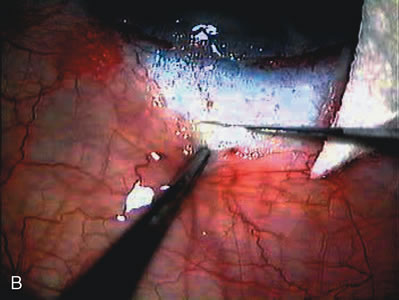

The inflammation associated with lens extraction at any site usually causes complete failure of a marginal functioning bleb. In addition, pressure reduction by medical means is usually minimal in these recalcitrant cases, and combined surgery is indicated. In the past, these cases were approached with large-incision ECCE, clear corneal cataract incision, and bleb revision. Drawbacks included those mentioned earlier for large incision clear corneal cataract extraction, and bleb revision is often associated with conjunctival buttonholes, wound leaks, subconjunctival hematoma, destruction of friable sclera, and associated hypotony. With the advent of modern-day cataract surgery, a phacotrabeculectomy is often possible adjacent to the failed filter (Fig. 7). The ability to combine cataract extraction with implant and filtration surgery all through the same small incision has greatly improved outcomes for patients with marginal preoperative filters. There are several other viable options in this case. If the surgeon elects to remove the cataract through a temporal clear corneal incision, the bleb may be revised or a new adjacent filter fashioned. As mentioned earlier, revising a failed filter is technically challenging. If the surgeon believes it is not feasible to revise the filter or fashion a new one, a glaucoma drainage implant is a reasonable option combined with temporal lens extraction.172

Fig. 7. Phacotrabeculectomy adjacent to a failed filter in cataractous eye. The ability to combine small-incision cataract extraction with trabeculectomy all through the same incision adjacent to the failed filter allows the surgeon to work in a familiar superior area. Avoiding incisions into the existing bleb decreases conjunctival buttonholes, hypotony, operating room time, and subconjunctival bleeding. A. Appearance of failed bleb with exposure of superior temporal quadrant gained with a corneal traction suture. B. Prepare a limbus-based conjunctival flap and a scleral flap. C. This bleb is at high risk to fail again justifying the need for MMC, 0.2 mg/cc applied on a pledget for 4 minutes. D. Insert the keratome and perform phacotrabeculectomy in the usual fashion.